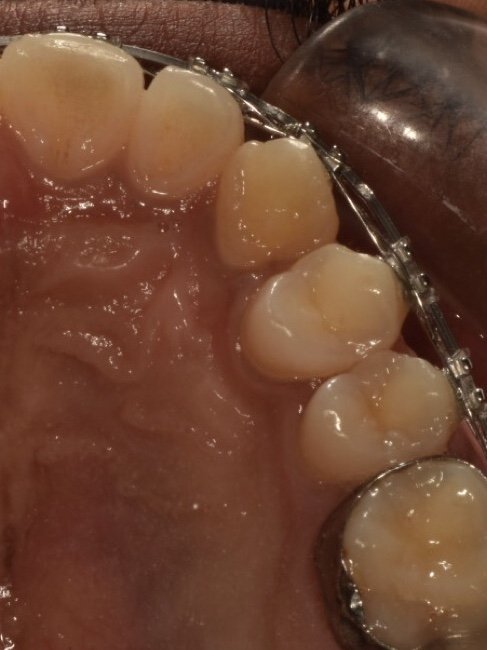

Arch expansion therapy

Craniofacial Orthopedics